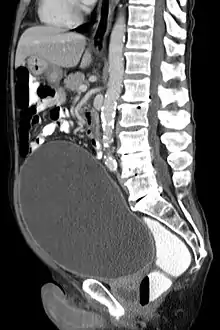

CT scan in the sagittal plane which reveals a greatly enlarged urinary bladder caused by urinary retention, a condition which often leads to overflow incontinence.